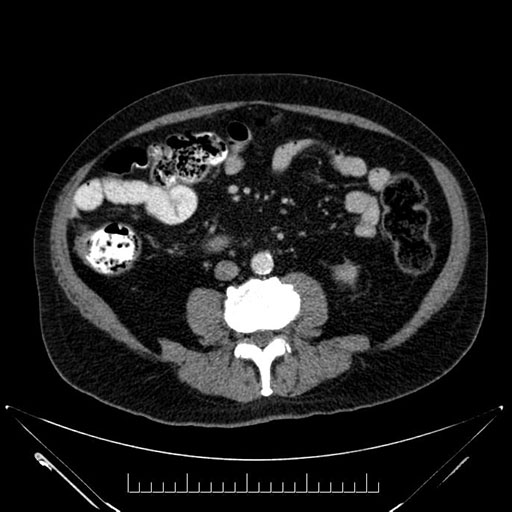

Imaging Analysis

Look through the patient's CT scan to identify any areas of concern for the necessary procedure.

Based on your CT findings, which issue(s) would give reason for "planned slowing down moment(s)" in this case?